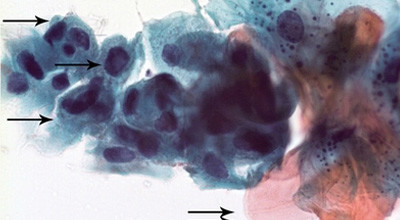

Das zytologische Bild zeigte viele Plattenepithelzellen mit Parakeratosezeichen und Kerndysplasien (Abb. 2 bis 4). Aufgrund dieser deutlich pathologischen Befunde wurde zusätzlich eine quantitative DNA-Analyse (DNA-Zytometrie) durchgeführt. Das DNA-Histogramm zeigte zwei klare aneuploide Stammlinien im S-Phasen- und 4c-Bereich sowie drei Kerne mit einem DNA-Gehalt über 9c (Abb. 5). Infolge des hochgradig atypischen DNA-Verteilungsmusters konnte eine (mittlere bis schwere) Dysplasie bzw. gar Carcinoma in situ im betroffenen Schleimhautbereich nicht ausgeschlossen werden. Aufgrund dieser Befunde wurde nach Rücksprache mit dem Patienten beschlossen, die Zungenläsion in toto zu exzidieren. Nach terminaler Anästhesie der Zunge links (Ubistesin© 4%, Articaini hydrochloridum, 3M ESPE AG, Seefeld, Deutschland), erfolgte die Exzision mit dem CO2-Laser (Luxar LX-20, Novapulse Laser, OpusDent Ltd., Santa Clara, CA, USA) mit einer Wellenlänge von 10,6µm und einer mittleren Leistung von 5 Watt im Superpuls-Modus (Pulsdauer 25ms, 30 Pulse pro Sekunde) (Abb. 6 bis 8). Das Exzisat wurde in eine 4%ige gepufferte Formalinlösung eingelegt und an das Institut für Pathologie der Universität Bern gesandt. Auf die offene Wundregion wurde postoperativ eine Adhäsivpaste (Solcoseryl Dental Adhäsivpaste, Valeant Pharmaceuticals GmbH, Birsfelden, Schweiz) aufgetragen und dem Patienten empfohlen, diese Paste mehrmals täglich während zwei bis drei Wochen auf das Wundgebiet zu applizieren.